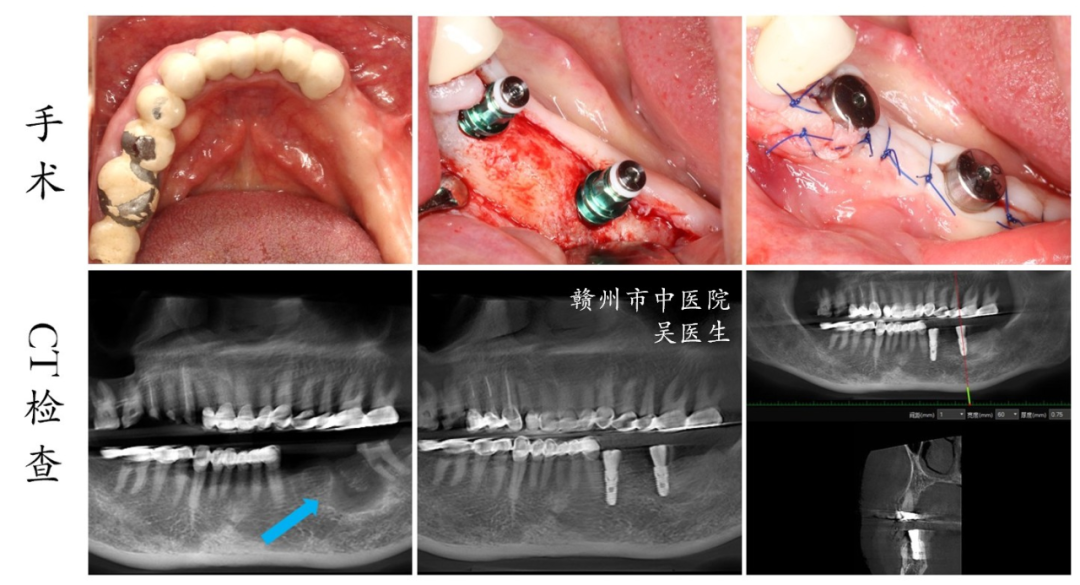

1.CT在种植治疗中的应用

CT检查在种植牙过程中扮演着重要的角色,可以提供详细的口腔和颌面部结构信息,为种植牙手术的规划和执行提供准确的引导,提高种植成功率,并避免可能带来的神经或血管损伤。